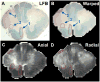

Methods: DTI was performed at 4.7 T on 9 MS and 5 normal control fixed cervical spinal cord blocks following autopsy. Sections were then stained for Luxol fast blue (LFB), Bielschowsky silver, and hematoxylin and eosin (H&E). Regions of interest (ROIs) were graded semi-quantitatively as normal myelination, mild (<50%) demyelination, or moderate-severe (>50%) demyelination. Corresponding axonal counts were manually determined on Bielschowsky silver. ROIs were mapped to co-registered DTI parameter slices. DTI parameters evaluated included standard quantitative assessments of apparent diffusion coefficient (ADC), relative anisotropy (RA), axial diffusivity and radial diffusivity. Statistical correlations were made between histochemical gradings and DTI parameters using linear mixed models.